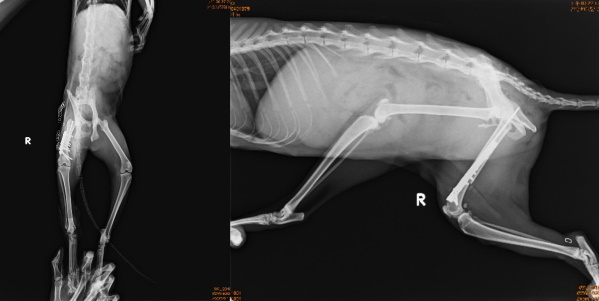

主題: 宜蘭收容所全身撕裂傷的小宜 申請者姓名: 臺北市支持流浪貓絕育計劃協會 花色: 申請日期: 2015-03-25 14:16:43 申請者部落格: 申請者臉書網址: 所在縣市/合作醫院: 台北市/沐恩動物醫院 治療費用: 78862元 需求人數: 81人 已結案 (2021-06-03 00:05:07) 報名人員: Amelie Chiang x3(已付款)、PeiPei(已付款)、bbfish1224(已付款)、QQ(已付款)、裘爸(已付款)、Miao Mie Mie(已付款)、vopoo、yen36(已付款)、Jill S.(已付款)、Chris Chen x2(已付款)、Jill S.、芳芳(已付款)、claire x3、claire x5、claire x5(已付款)、Ariel Hsu(已付款)、Forest(已付款)、Forest(已付款)、咪寶的阿木 x10(已付款)、小黃、小黃(已付款)、Lynn Wu x3(已付款)、陳小茜(已付款)、Becca Huang(已付款)、Sunny Chen(已付款)、larina(已付款)、Erica Wu(已付款)、Jessie(已付款)、Cheer(已付款)、MAC創意人偶活動公司 x2、Sherry Ko(已付款)、道森(已付款)、媽咪陳(已付款)、FAT5 x2(已付款)、若(已付款)、BigMao(已付款)、Yu-Ling Chang x5(已付款)、龐達安 x5、小涵 x2(已付款)、陳咩寶(已付款)、VVHSU(已付款)、Alisa Huang(已付款)、Karen(已付款)、MAC創意人偶活動公司 x2(已付款)、Mai Lin Lai x2(已付款)、Willy Hu(已付款)、Mei Mei Liao(已付款)、劉大妞(已付款)、sandroio(已付款)、Norman Wu(已付款)、Eu Gene(已付款)、Amber Chung(已付款)、Amber Chung(已付款)、Jessica Chen(已付款)、Hide x2(已付款)、ERic YU(已付款)、Nadia Huang(已付款)、Shelby Huang、Tien-Yin Ku x3(已付款)、戀糖bear(已付款)、 候補人員: Queena Wang、Winnie Lu、 動物病情說明: 1/27宜蘭收容所通知,有隻貓咪像破布娃娃一樣身上腳上多處撕裂傷,緊急前往帶出就醫,鎮定檢查傷口小腿以下及背部皮膚缺損嚴重予以清創,並拍攝X光片發現右大腿骨折,,因傷口有感染的狀況,要等感染控制才能進行縫合,期間先給與包紮避免接觸感染,2/5日進行大腿骨骨折修復手術,2/12進行小腿皮膚缺損皮瓣修復手術並裝置引流球,所幸貓咪尚年幼復原狀況良好,2/24進行最後階段手術背部皮膚傷口縫合,並持續給與鈣和骨骼生成針劑幫助骨骼生長癒合,3/12日貓咪狀況穩定拆線出院回安養之家繼續修養至骨骼完全生長,醫療費用還請各位幫忙。